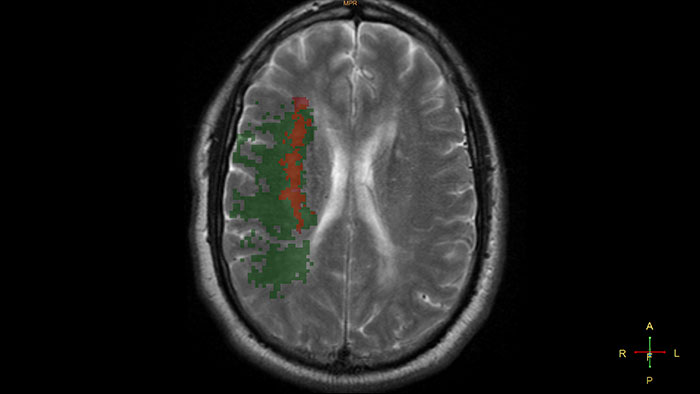

Gain an optimized view of the body’s most complex organ

Supports the visualization of brain images for the evaluation and monitoring of changes across multiple time points. The application performs automatic registration between studies and provides semi-automatic segmentation and editing tools for volumetric measurement of brain lesions.